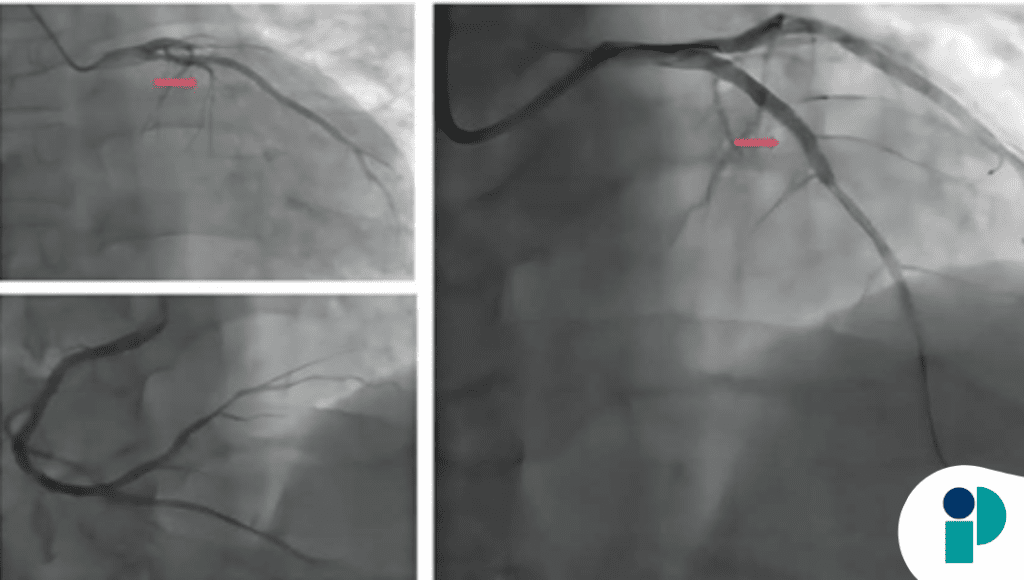

El paciente acudió por disnea progresiva y malestar general, sin que refiriera dolor torácico. Los exámenes iniciales revelaron elevación de marcadores cardíacos y alteraciones en el electrocardiograma, lo que orientó hacia un infarto de miocardio con elevación del ST. La ecocardiografía y la resonancia magnética cardiaca demostraron trombos extensos en ambos ventrículos, una complicación infrecuente pero grave, particularmente en ausencia de síntomas clásicos.

Aunque la trombosis ventricular suele asociarse con infartos grandes o con disfunción segmentaria marcada, la ausencia de dolor en este caso complicó la presentación clínica. Los autores señalan que el infarto silente puede retrasar el diagnóstico y permitir que se formen coágulos voluminosos dentro de las cámaras cardiacas, con riesgo de embolias sistémicas o falla cardiaca.